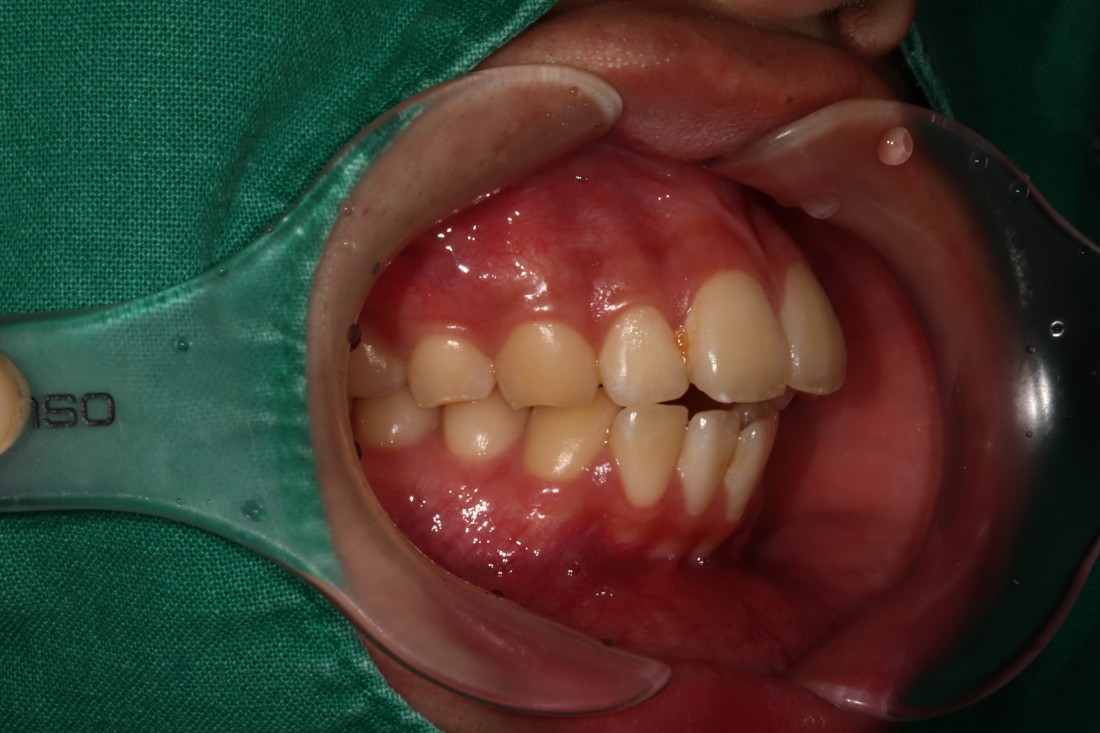

광주 개방교합 교정을 위해

방문해주신 30대 남성 환자분의

교정 전 사진입니다.

어금니를 맞닿게 하여서 입을 다물어도

윗니와 아랫니가 만나지 않는데요.